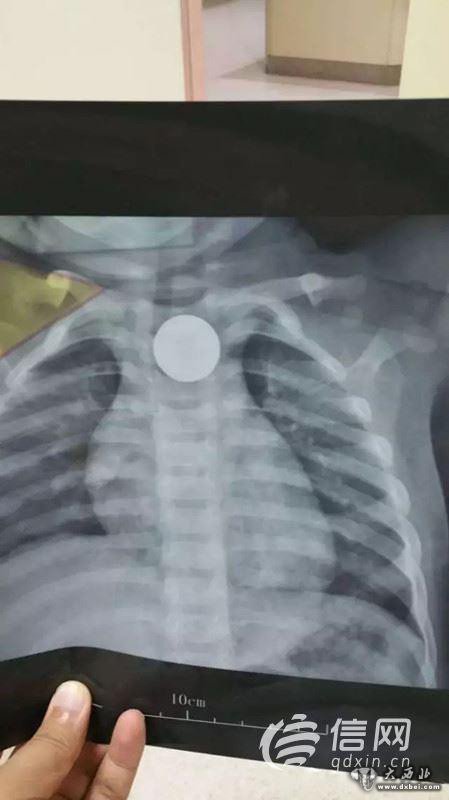

7月12日晚10:20,一名家长抱着一个14个月大的孩子急匆匆走进青岛市妇女儿童医院耳鼻喉科急诊值班室。“5个小时前孩子误吞下了一枚遥控器的直径为2.2cm的纽扣电池,我们当地医院确诊为电池卡入食道。”

晚上11点10分,患儿被送入手术室,麻醉师和护理人员一边安抚患儿,一边进行麻醉处置和各项护理操作,整个手术间弥漫着紧张的气氛。“因为患儿年龄太小,最小号的食道镜在进入食道时也遇到了很大的阻力,2.2厘米大的异物只能和食道镜一起撤出。”经过手术医生的反复努力,发现电池卡在食道入口下方约2厘米处,电池被顺利取出,此时在场的医护人员松了一口气。